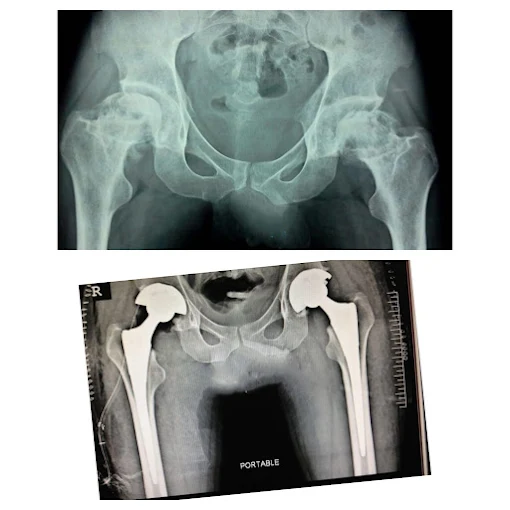

Hip & Knee Replacement

Comprehensive joint replacement solutions using modern implants

Image Gallery

Yes, Dr. Sachin Sonawane is a highly experienced knee replacement surgeon wakad pune and hip replacement surgeon wakad pune, performing advanced joint replacement procedures at Wakad, Pune using modern implants to restore mobility and reduce chronic joint pain.